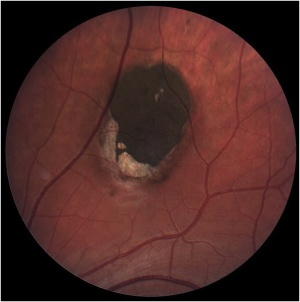

Solitary CHRPE is typically a single, flat, round, hyperpigmented retinal lesion (Image 1). Color may vary from light gray to brown or black, with smooth or scalloped margins. There is typically a sharp demarcation between CHRPE and adjacent normal RPE, with a normal appearance of the overlying retina and vasculature. Lesions are generally located equatorially, with a predominance in the superotemporal quadrant, but may be located throughout the fundus.[10] Macular involvement is rare. Size varies from 100 μm to several disc diameters.[10] The lesion may be surrounded by a marginal depigmented halo or contain multiple hypopigmented lacunae. These hypopigmented areas show a tendency to enlarge slowly over time.[7][14]